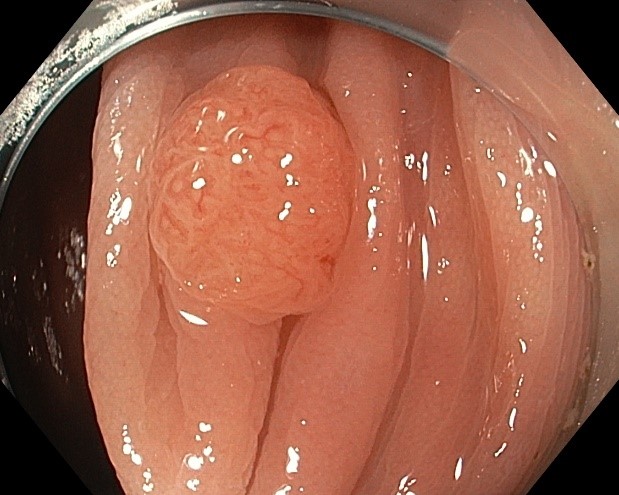

Колоноскопия является золотым стандартом диагностики и малоинвазивного лечения заболеваний толстой кишки, в том числе раннего рака и его предшественников (полипов). В целях профилактики рака толстой кишки колоноскопия показана всем после 40 лет, в среднем каждые 5 лет. Для достижения качественной подготовки толстой кишки к эндоскопическому исследованию и/или операции крайне важно строгое соблюдение всех этапов данных рекомендаций.

Соблюдение рекомендаций позволяет качественно провести исследование и выявить даже небольшие полипы

Соблюдение рекомендаций позволяет качественно провести исследование и выявить даже небольшие полипы